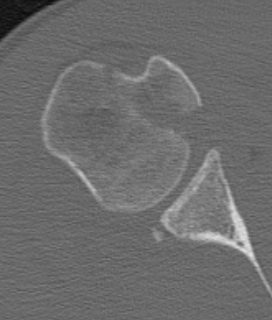

CT scan

Confirms dislocation

Reverse Hill Sachs

Humeral head defect

- caused by impaction of anterior humeral head on posterior glenoid

- intra-articular

- measured as a percentage of the articular surface

Lesser tuberosity fractures

Posterior glenoid fractures / bony bankart